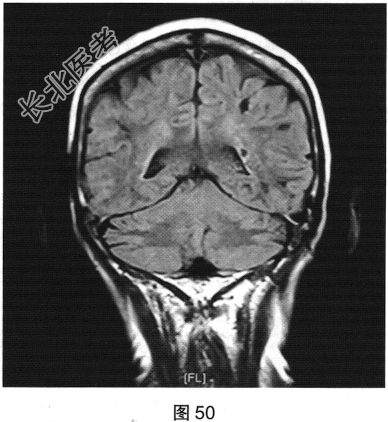

- 多项选择题2.[提示]患者行FLAIR、DWI及增强扫描,见图45~图54。该患者MRI影像的主要阳性表现有( )

C、双侧放射冠及半卵圆中心多发条状、圆形及卵圆形异常信号灶

E、病灶呈长T1、长T2信号,FLAIR为低信号,DWI为低信号,ADC为高信号

B、病灶在所有MRI序列上均有脑脊液信号相似

C、是与穿动脉伴行的含有间质液体的由柔脑膜细胞包绕的囊性结构,与蛛网膜下腔相通